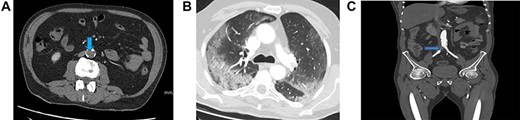

Blood investigations showed an elevated WCC, a low lymphocyte count and elevated CRP. His prothrombin and thrombin times were also prolonged (Table 1). A CT scan demonstrated filling defects in the descending thoracic and abdominal aorta (Fig. 2A) and superior mesenteric artery (SMA) suggestive of acute thromboembolic phenomena. There was no sign of ischaemic bowel. A wedge-shaped peripheral hypodensity was seen at the mid-pole of the left kidney (likely to be a renal Infarct) (Fig. 2B). A CT of the chest showed patchy and ground-glass shadowing (Fig. 2C).

(A) Filling defect in aorta (blue arrow). (B) Left renal infarct (blue arrow). (C) CT-thorax showing pulmonary changes. (D) Thrombus in the distal SMA (blue arrow)

A repeat CT showed a SMA thrombus (Fig. 2D). Urgent angiogram and catheter-directed thrombolysis of the SMA was unsuccessful and the decision was made to operate. Exploratory laparotomy revealed a gangrenous segment of ileum necessitating resection of ~30 cm of small bowel. Re-look laparotomy at 48 hours showed no progression of ischaemia and thus anastomosis of the bowel ends was performed.